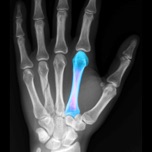

BoneGauge allows you to approximate an individual's bone density and quality from a mobile platform. BoneGauge helps you make measurements of cortical thickness of the second metacarpal from either hand or wrist x-rays. Use your smart phone camera to take a photo of the second metacarpal on an x-ray, or make measurements from an image saved in your photo library.

BoneGauge accurately calculates 2nd metacarpal cortical percentage (2MCP) in a semi-automated fashion. 2MCP has been shown to correlate with hip bone mineral density and T scores from DXA scans. Measurements made in the app will be uploaded to a central database. When combined with a patient's age, gender, and DXA score, past measurements will also help the improve the accuracy of future measurements.

This app allows you to estimate an individual's global T score in an office or hospital setting, by simply taking a photo of the 2nd metacarpal. While this measurement may not completely replace DXA, it may help a clinician screen a patient's bone quality to assist in treatment decisions and determine who may benefit from further bone density testing or osteoporosis treatment.

• Screenshot #3 pour BoneGauge